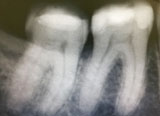

Digital X-rays

At the VSmile dental clinic we have an intraoral digital camera with CCD sensors, that produces high quality digital x-rays whilst exposing the patients to the least amount of radiation possible, 80-90% less than usual x-rays.

The x-rays are shown on the computer screen in a fraction of a second, without any delay at all, unlike the classic type x-rays.

From the digital x-rays we can collect important information regarding the state of the teeth and jaws, and as such we can see whatever we are able to with a simple clinical exam, that makes a complete and accurate diagnosis.

Using visualix we are able to process the image, and can simulate a 3D image that cna be used to take measurements, which lowers the timeframe needed to work, and increase the quality of treatment.